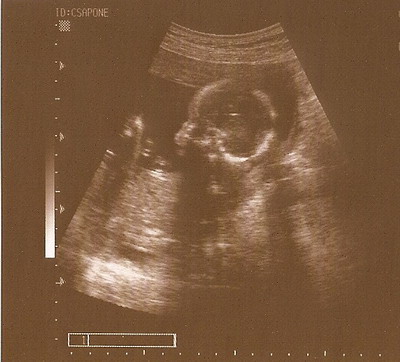

Ercsi nagyon édes Csipetke :D Néztem a méreteit, kicsit nagyobb mint Mazsi, de szerintem ez azért van mert 4 nappal később voltatok :wink: Ezek szerint gyakorlatilag hajszálra egyidősek :D

Ercsi - Cukik a képek :)

Nem olyan régen láttam ugyan .. de az utolsó kötelező Uh meg sem közelítette a 16 hetes 4D-t .. :roll: :roll: Az meg már nagyon nagyon régen volt ... :roll: